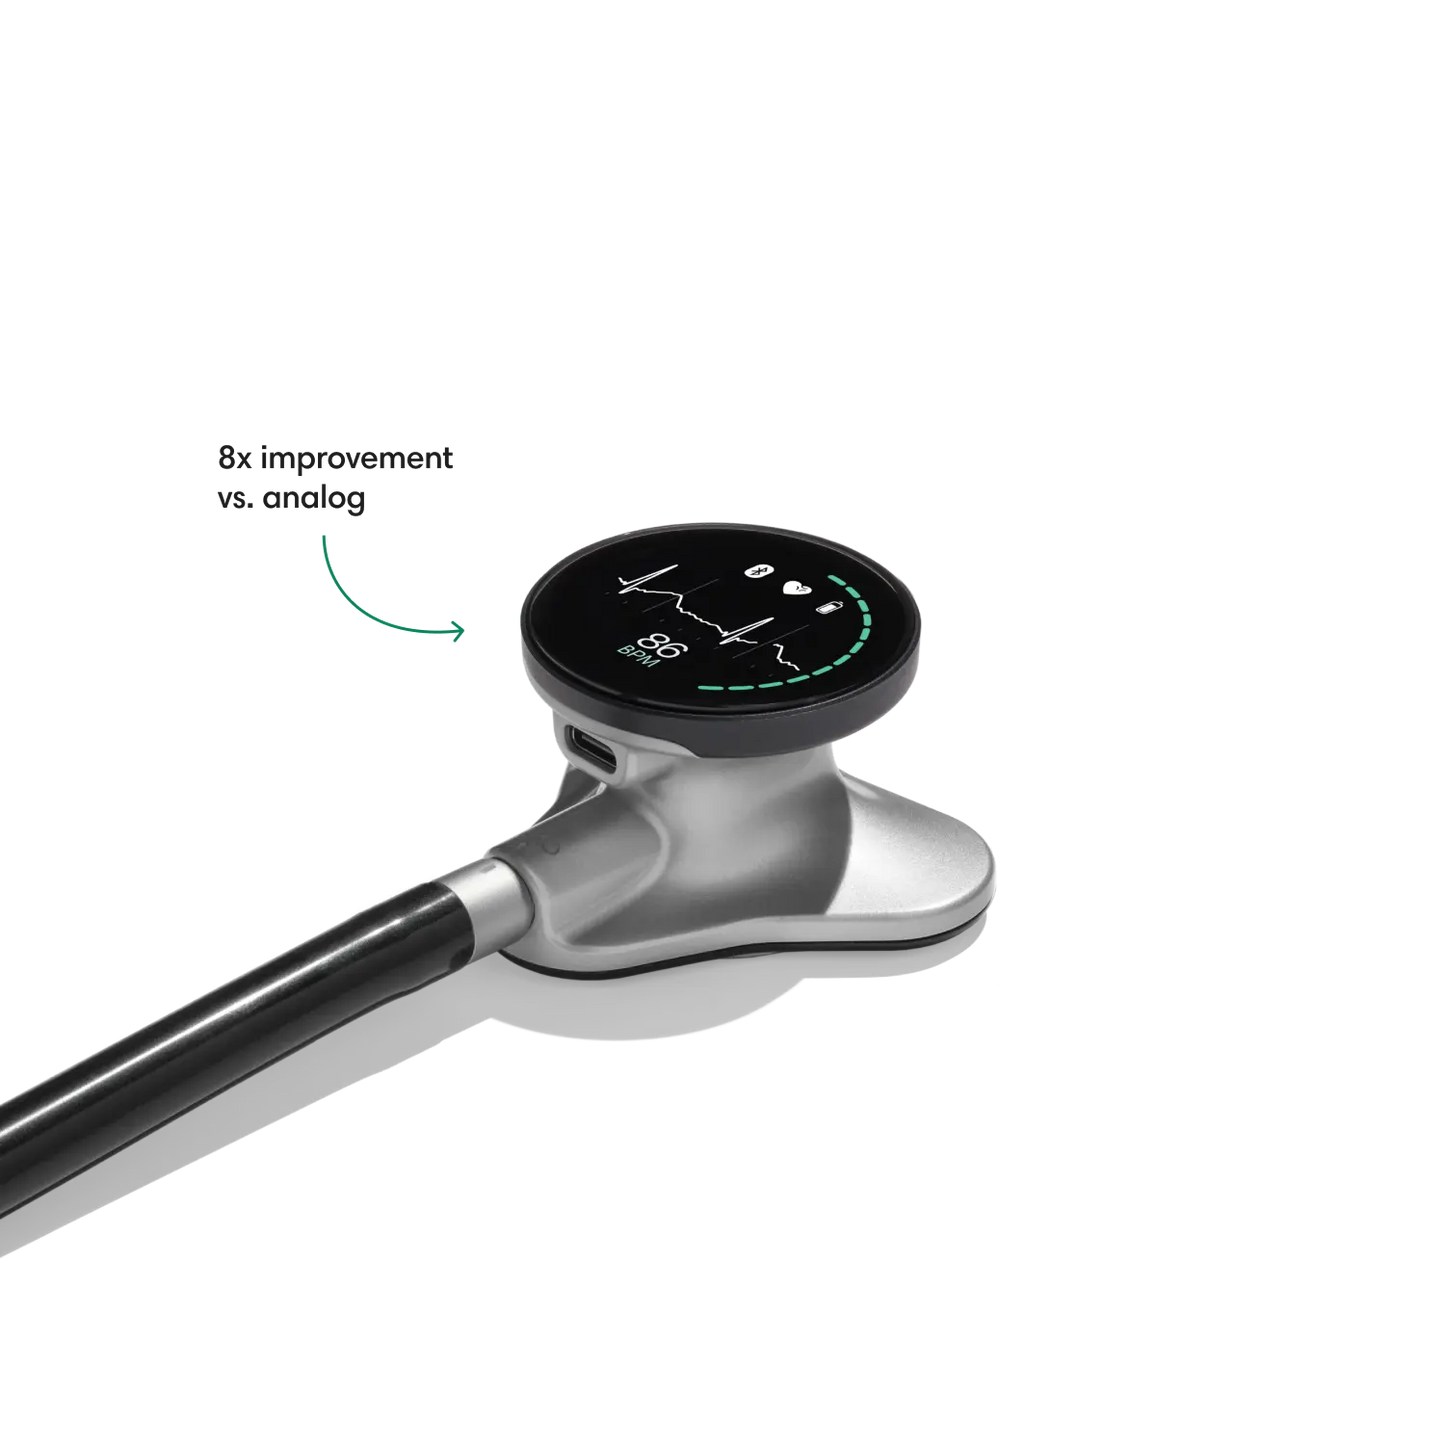

Instead of using a hollow tube like with an analog stethoscope, heart and lung sounds are delivered digitally through ear tip speakers. This results in unparalleled audio quality and sound cancellation.

- Reduces background noise 8x better vs. a typical analog stethoscope.